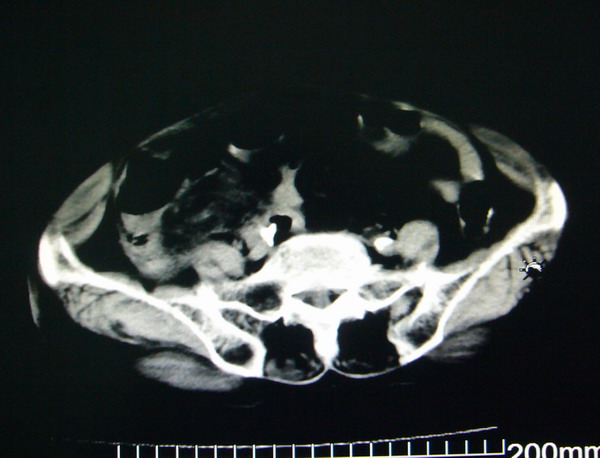

女:83y,转移性右下腹痛2小时,白细胞计数增高。

1.右侧肾盂扩大,肾盏无扩张,考虑:先天性肾盂变异可能性大。

2.胆囊扩张,考虑:胆囊炎。

3.阑尾区域可见以结节样高密度影,结合病史,考虑:阑尾结石,阑尾炎。

右下腹肠系膜增厚,结合病史支持阑尾炎.

右侧壶腹型肾盂可能,建议输路造影或增强

1.右侧肾盂扩大,考虑先天性肾盂变异或肾盂旁囊肿。

2.胆囊扩张,考虑胆囊炎。

3.阑尾区域可见结节样高密度影,结合病史考虑:阑尾结石、阑尾炎。